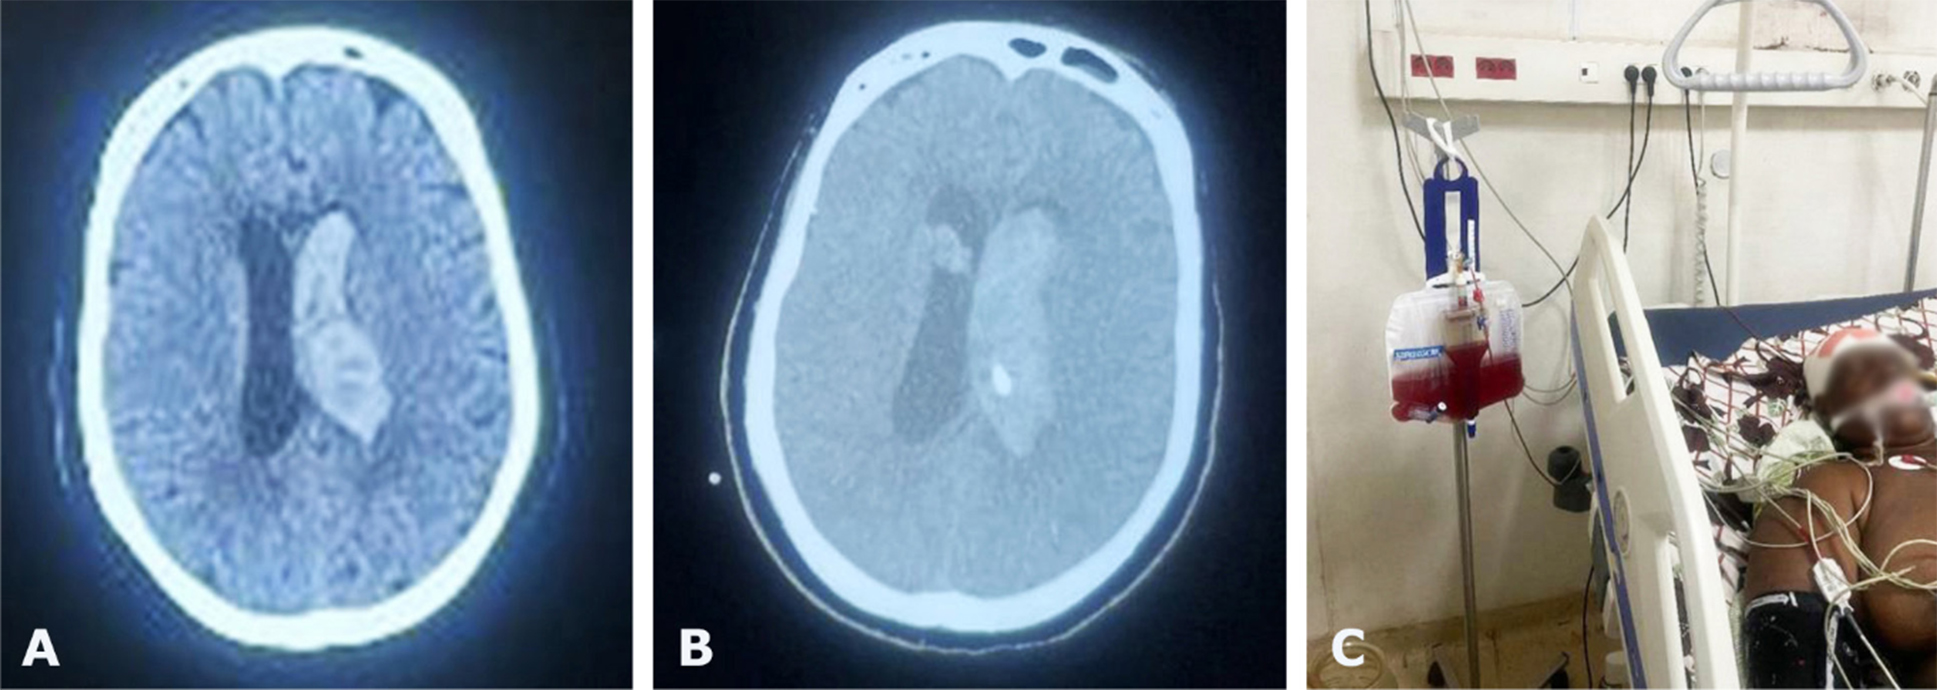

During the study period, a total of 63 patients were admitted for spontaneous ICH and IVH was associated in 24 (38.1%) patients. Among them, EVDs were placed in 17 patients. The mean age was 49 years with range of 27 to 66 years. There were 11 males and 6 females. The main risk factors of stroke were hypertension in 13 patients and diabetes in 7 patients. The initial GCS was between 5 and 8. Unilateral pupillary dilatation was found in 8 patients (Table 1). EVD was placed in frontal horn in the lateral ventricle in all cases (Fig. 1, 2) and continuous CSF drainage was indicated leading to ventricle size and blood clot removal (Fig. 2, 3). The duration of EVD was 1 to 8 days. Four (23.5%) patients experienced infection as a complication. The short-term mortality rate was 70.5 % at 30 days including 8 males and 4 females with a mean age of 53 years. The functional outcomes were poor in 4 patients with mRS sore of 4 and 5 (Table 2). The independent predictor factors for 30-day mortality (Table 3) were poor GCS (p=0.319), mydriasis (p=0.245) and poor Graeb score (p=0.004).

Fig. 3. Preoperative CT scan showing IVH (A) and postoperative CT scan showing the complete evacuation of IVH after EVD (B) with the burr hole in 3D (C)